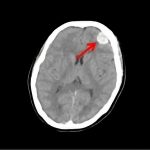

断層撮影